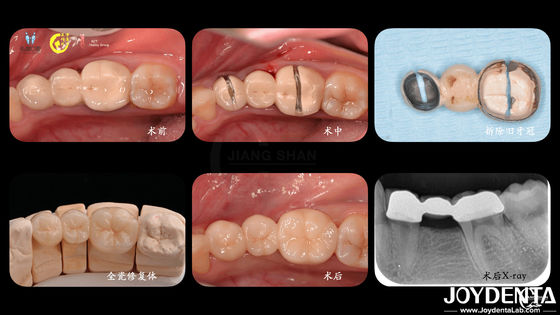

Perfecte tanden Zirconia tandkronen met CAD CAM-systemen voor precisieproductie

CAD/CAM-compatibele Zirconia tandheelkundige kronen Precision Manufacturing voor op maat gemaakte kleuren en maten

Tandkronen van zirconia duurzaam en geschikt voor achter- en voorrestoraties